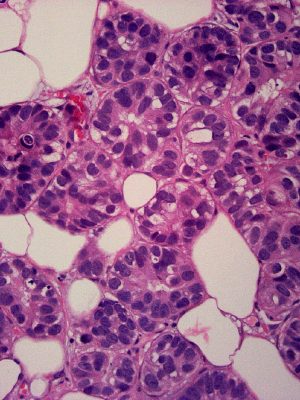

Gynecologic & Breast Pathology

Dr. Ramdall has specialized expertise in the diagnosis of various gynecological and breast disorders, including:

• Benign and malignant neoplasms